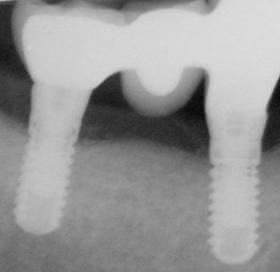

Féléves kontroll felvétel a regeneratív műtét után. A csontkráter kitelődött csonttal, azaz a defektus meggyógyult